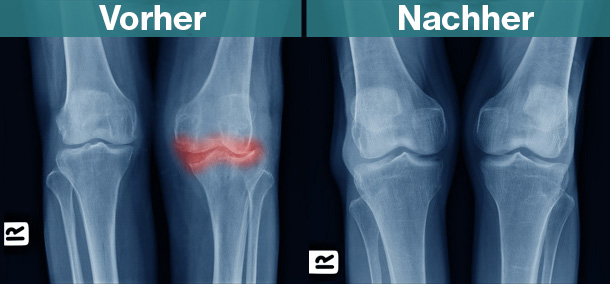

Mit dem Harz des Weihrauchbaumes stoppen Sie Entzündungen in Ihrem Körper, bevor sie chronisch werden Das bedeutet: Der Boswellia serrata-Extrakt wirkt so stark, dass er sogar die klassischen Entzündungshemmer wie Ibuprofen und Diclofenac aus dem Rennen wirft. Forscher der Friedrich-Schiller-Universität Jena entdeckten, warum Weihrauch Entzündungen ausbremst. Sie konnten den Einfluss von Boswellia auf ein spezielles Enzym, die 5-Lipoxygenase, entschlüsseln. Statt die Entzündung zu befeuern, produziert dieses Enzym unter dem Einfluss von Boswelliasäure entzündungsauflösende Substanzen. Das heißt, vereinfacht gesagt, der Weihrauchinhaltsstoff programmiert das Entzündungsenzym zu einem entzündungsauflösenden Enzym um. Entscheiden Sie sich jetzt für das natürliche Powerduo unter den Entzündungs- und Schmerzkillern: Weihrauch und Lycopin Die gesundheitsfördernde und entzündungshemmende Wirkung von Lycopin ist vielseitig. Der Pflanzenstoff aus der Gruppe der Carotinoide stärkt das menschliche Immunsystem, indem er das Wachstum und die Aktivitäten bestimmter Immunzellen unterstützt. Mit der Nahrung kommt er vor allem in Tomaten und Hagebutten vor. Powergelenkstoff Nummer #4: Vitamin C Vitamin C ist die Königin unter den Vitaminen. Aus gutem Grund. Aber haben Sie schon vom außerordentlich wirksamen Effekt von Vitamin C auf Ihre Knie-, Schulter- und Hüftgelenke gehört? Nach Einnahme wirkt Vitamin C direkt im Gelenk. Es baut dort gesunde Knorpelstrukturen auf. Und hält Ihr Gelenk dauerhaft elastisch. Powergelenkstoff Nummer #5: Kennen 73% der Japanerinnen keine Osteoporose wegen dieses Lebensmittels aus dem Meer? Diese Meeresalge hat einen sensationellen Effekt auf Ihre Gesundheit. Sie enthält mehr als 32 seltene Spurenelemente (z. B. Jod, Selen, Zink, Kobalt, Kupfer und Chrom): Die Rede ist von der Rotalge (Lithothamnium). Sie ist für die Remineralisierung des menschlichen Organismus verantwortlich. Zusammen mit ihrem hohen Kalziumgehalt wirkt Sie einem Kalziummangel entgegen. Aktuelle Studien zeigen, dass Lithotamnium im Körper dafür sorgt, dass die Knochenstruktur erhalten bleibt. Was wäre, wenn Sie alle die eben genannten effektiven Powergelenkstoffe in einem einzigen Präparat zu sich nehmen könnten? Und damit einen wahren Gelenk-Gesundmacher zu sich nach Hause holen? Das Geheimnis liegt in diesem simplen Glas Wasser. Nehmen Sie ein gewöhnliches Wasser Glas und nehmen Sie eine Kapsel ARTRO 441-Kapsel. Ja, ARTRO 441, so heißt die neue Innovation der Arthrose-Forschung. Ärzte und Patienten jubeln „Sie funktioniert. Und wie!“ Und Sie sind herzlich eingealden, es jetzt selbst zu erleben. So spülen Sie den Schmerz einfach weg! Mit diesem Getränk führen Sie Ihrem Körper auf ganz bequeme Weise die wichtigsten Powergelenkstoffe zu, die er braucht, um Schmerzen zu lindern. Sie spülen Entzündungen weg, bevor sie chronisch werden. Während Produkte aus dem Drogeriemarkt wie z. B. Vitamin C-Pulver, Weihrauchcreme, Hyaluronpräparate und Co. dauerhaft nur auf den Geldbeutel schlagen und das ohne nennenswerte Erfolge für Ihre Gesundheit, wirkt ARTRO 441 Extra besser und stärker als alle anderen Mittel. Schauen Sie nur, wie der Knorpel vor und nach der Anwendung mit dem Gelenkvitalstoff ausschaut! ARTRO 441 Extra vereint die wirksamsten Nährstoffe zur Regeneration und zum Wiederaufbau Ihrer Gelenksubstanz sowie zur dauerhaften Beseitigung Ihrer Schmerzen. ARTRO 441 Extra ist ein wahrer Gelenk-Verjüngerer, weil er die wichtigsten Powergelenkstoffen für Ihren Knorpel Glucosamin und Chondroitin, Vitamine und sekundäre Pflanzenstoffe, in perfekter Dosierung (viele Produkte, die Sie im Handel kaufen können, sind hoffnungslos unterdosiert) für Ihren Körper bereitstelt. Wie soll Ihr Leben in den nächsten Wochen, Monaten und Jahren aussehen? Möchten Sie sich ein persönliches Geschenk machen? Oder wollen Sie zu den Unglücklichen gehören, deren Schmerzen chronisch geworden sind? Was bedeutet, dass sie über Wochen oder Monate ausgeschaltet sind, und Sie haben es jetzt in der Hand! Heute ist der entscheidende Wendepunkt in Ihrem Leben. Heute machen Sie sich unabhängig von gefährlichen Schmerzmitteln und dubiosen Therapien, wie den hoffnungslos überteuerten und wenig wirksamen Hyaluronspritzen, die Ihnen Ihr Arzt aufdrängt. Ab heute lachen Sie Ihrem Arzt ins Gesicht, wenn er Ihnen eine Knie-Operation empfiehlt. Sie werden voll Erleichterung ausrufen können: „Ich habe es geschafft! Ich habe meine Arthrose ein für alle Mal besiegt!“ Starten Sie jetzt mit ARTRO 441 Extra durch und erleben Sie, wie einfach es ist, Ihre Schmerzen loszuwerden. Klicken Sie jetzt hier und sichern Sie sich noch heute Ihre Kur. Monika Brockmann, 53, aus Düren, die ihre Freizeitbeschäftigungen vor lauter Schmerzen zwei Jahre pausierte: Ich hatte in beiden Knien Arthrose vierten Grades. Nach einer langen Autofahrt waren die Schmerzen im Knie, in der Wade und im Fuß kaum auszuhalten. Schmerzmittel wirkten nur kurz. Bis ich vor circa einem Jahr zufällig auf ARTRO 441 Extra gestoßen bin. Ich war erst skeptisch, aber nachdem ich 23 Tage diese Therapie gemacht hatte, waren meine Schmerzen wie weggeblasen. Gehören Sie auch ab sofort zum Kreis der Glücklichen, die Ihre Gelenkschmerzen besiegt haben. Hermann P., 73, traut keinem Orthopäden über den Weg Vor ca. 4 Wochen startete ich meine erste ARTRO 441 Extra - Kur, weil mein Arzt mir ein künstliches Knie empfahl, ich aber unter gar keinen Umständen unters Messer möchte. Ich glaubte nicht so recht an die versprochene Wirkung, aber siehe da, tatsächlich sind die Schmerzen weitgehend verschwunden, obwohl ich pro Woche ca. 80'000 – 100’000 Schritte absolviere. Ich bin absolut glücklich, dass Sie mich vor einer Operation bewahrt haben. Christine G., 47, die alle Hoffnung auf Besserung Ihrer Arthrose aufgegeben hatte: Bereits im Alter von 43 erhielt ich die Diagnose Arthrose. Seitdem hatte ich ständig mit meinem Knie zu kämpfen und wurde nachts wach vor lauter Schmerzen. Zum Glück habe ich eine liebe Freundin, die mich auf ARTRO 441 Extra aufmerksam gemacht hat. Und was soll ich sagen: Kein anderes Mittel wirkt so gut wie dieses! Nach 10 Tagen konnte ich wieder entspannt durchschlafen. Ich habe sogar wieder mit dem Fahrradfahren angefangen. Feiern Sie mit uns Ihre Erfolge, die jetzt zum Greifen nah sind 14.580 Menschen leben durch ARTRO 441 Extra schon ihren Traum eines gesunden Lebens voller Vitalität und Freude. Werden auch Sie jetzt einer davon. Sie werden erstaunt sein, wie fit Sie sich fühlen. Null-Risiko-Garantie Mit der einzigartigen Naturheilkur ARTRO 441 Extra extra können Sie gar nichts falsch machen! Sie nutzen das Geheimnis gesunder Gelenke ab sofort für sich. Mit null Risioko- und 100% Erfolgsgarantie. Sichern Sie sich hier Ihre ARTRO 441 extra-Originalkur Rundum-Zufrieden-Garantie Sollten Sie mit Ihrer ARTRO 441 Extra-Kur nicht rundum zufrieden sein, senden Sie einfach die angebrochene Packung zurück – und Sie bekommen eventuell schon bezahltes Geld erstattet. Allerdings bin ich überzeugt davon, dass Sie ARTRO 441 Extra bald nicht mehr missen möchten, wenn Sie sehen, wie sich Ihre Lebensqualität spürbar verbessert. Und das ohne Spritzen, Operation und Nebenwirkungen. Ergreifen Sie die Chance noch heute. Testen Sie das Geheimnis gesunder Gelenke. Klicken Sie dazu einfach hier – und fordern Sie Ihre Test-Kur JETZT an. Herzlichst, Ihre Maria von Rohrer PS: Bitte beschließen Sie nicht erst auf dem OP-Tisch Ihr Leben zu ändern. Starten Sie jetzt den entscheidenden Schritt in Ihr gelenkgesundes Leben!